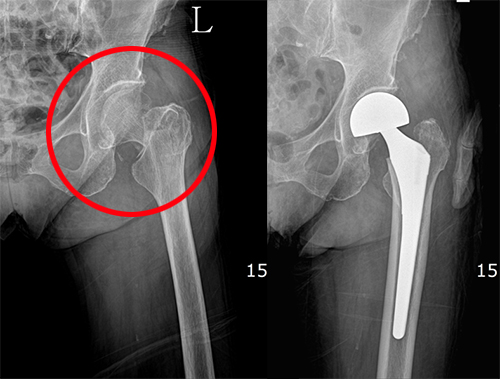

고관절 통증 증상 7. 골관절염

노화로 연골이 마모되면서 생기는 골관절염은 골절과 같은 관절 외상으로 발생될 수 있으며, 감염성 관절염으로 발생되기도 합니다. 이러한 골관절염은 고관절 통증 증상 원인이 되기도 합니다.

대퇴 경부 골절은 대퇴 골도로 가는 혈관이 손상되어 대퇴 골도의 무혈성 괴사와 불유합을 초래할 수 있기 때문에 응급으로 내 고정술을 시행하는 수술적인 치료가 필요합니다.